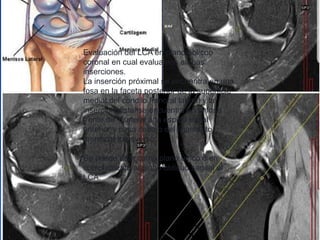

Evaluación del LCA en plano oblicuo

coronal en cual evaluamos ambas

inserciones.

La inserción próximal se encuentra en una

fosa en la faceta posterior de la superficie

medial del condilo femoral lateral y la

insercion distal se encuentra en la fosa

frente de Y lateral a la espina tribial

anterior y pasa debajo del ligamento

meniscal transverso.

Se puede usar como plano único o en

complemento al plano oblicuo sagital al

LCA.